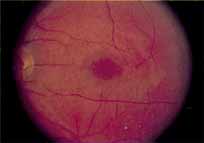

Although there is no reported genetic heterogeneity, there is wide phenotypic variation within the disorder. The major finding within the macula is a classic radial cystic maculopathy. Although retinal signs have been described in infants as young as 3 months, foveal schisis may be difficult to detect, leading to underdiagnosis. The diagnosis is usually not made until the affected male reaches school age (4 to 8 years of age) and encounters visual problems secondary to foveal involvement. Typical foveal schisis findings have been reported in 68% to 100% of eyes within various series.37,38 Foveal schisis is the only finding in about half the cases. It is characterized by the presence of radiate perifoveal microcysts located in the nerve fiber layer (Fig. 1) with radiate plications of the overlying internal limiting membrane that are seen especially well on monochromatic (red-free) photography (Fig. 2). The microcystoid change may slowly progress to form a macular cyst or hole. Foveal schisis has been reported in association with Goldmann-Favre vitreotapetoretinal dystrophy and rarely may be seen in rod-cone dystrophy or as an autosomal dominant or recessive condition.39–43